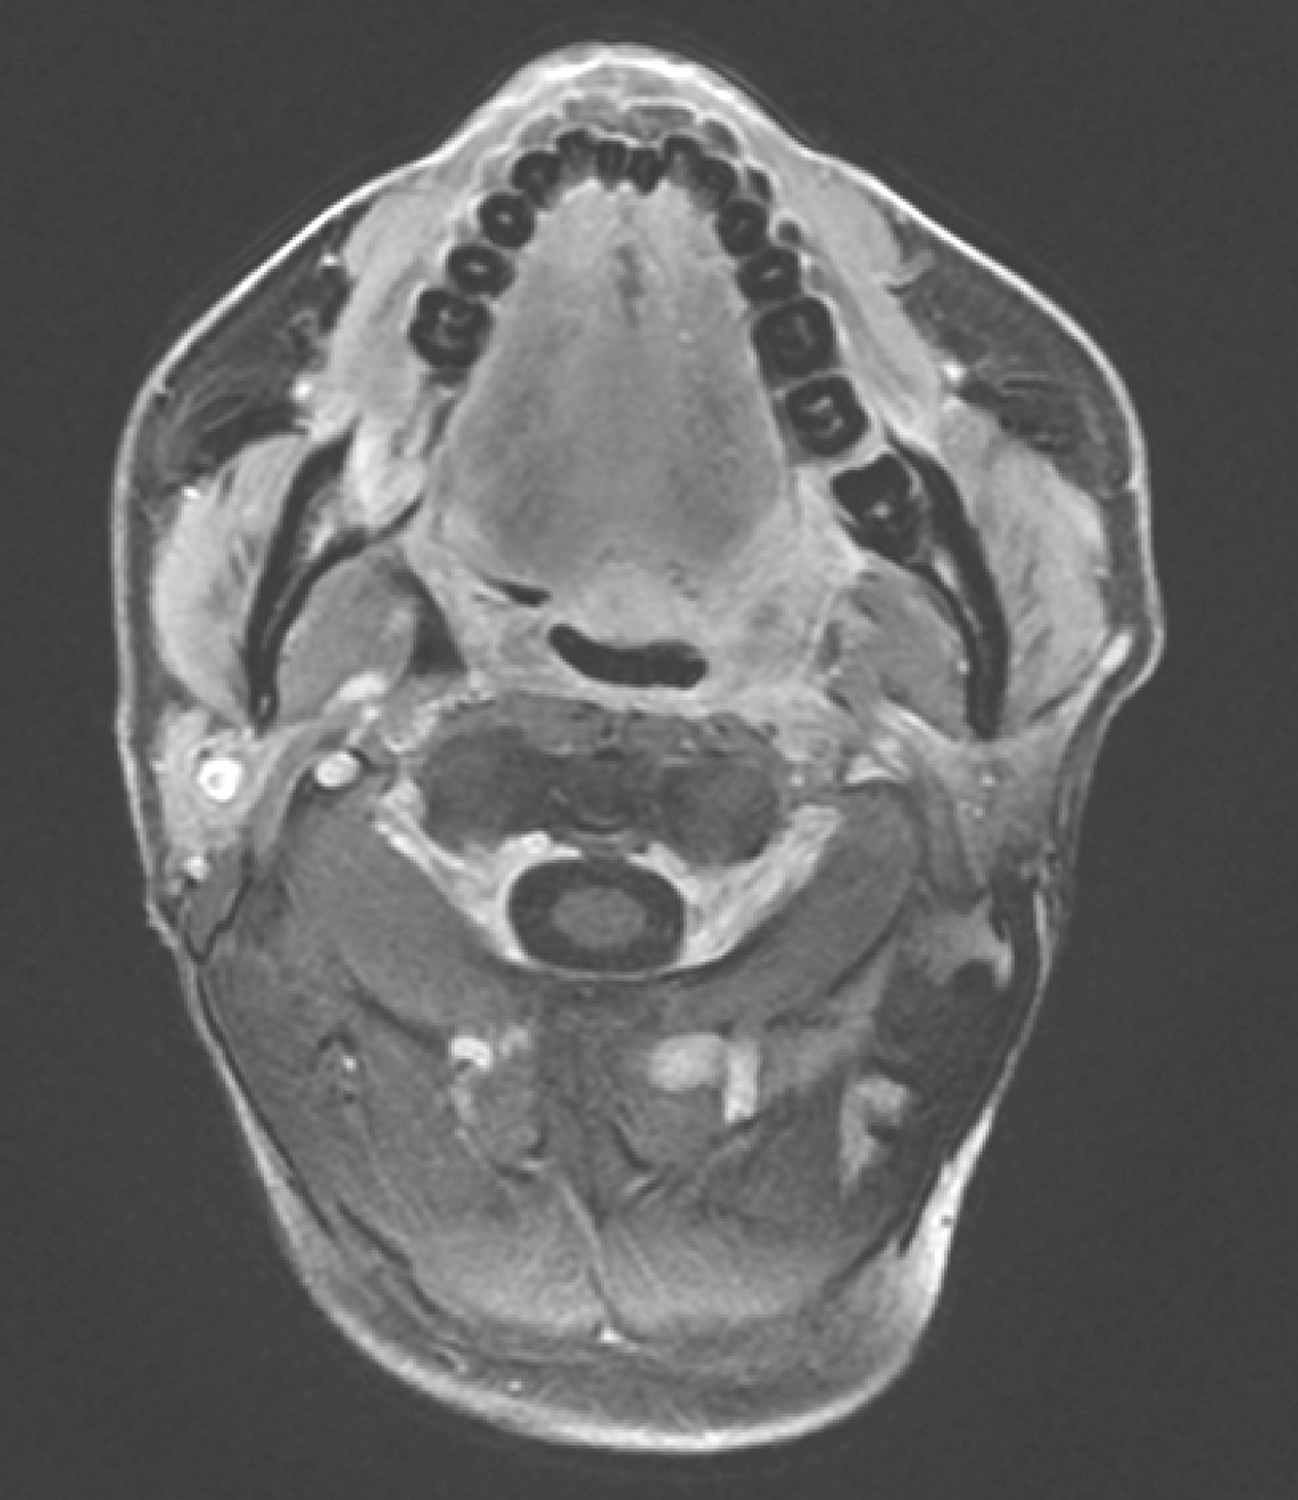

4.疗中评估

(1)2016年12月13日口腔MRI检查:“口咽癌同步放化疗中”复查,与2016年10月19日MR图像比较:①口咽左侧壁肿物,较前缩小,现大小约1.9cm×1.0cm,T2WI/FS呈稍高信号,增强扫描不均匀强化,肿物向外侵犯左侧咽旁间隙及左侧翼内肌,向下与左侧扁桃体关系密切(图6),请继续随诊。

②双侧颌下、颈深多发淋巴结,大者短径约0.7cm,请随诊。

图6复查口腔MRI示口咽左侧壁肿物较前缩小